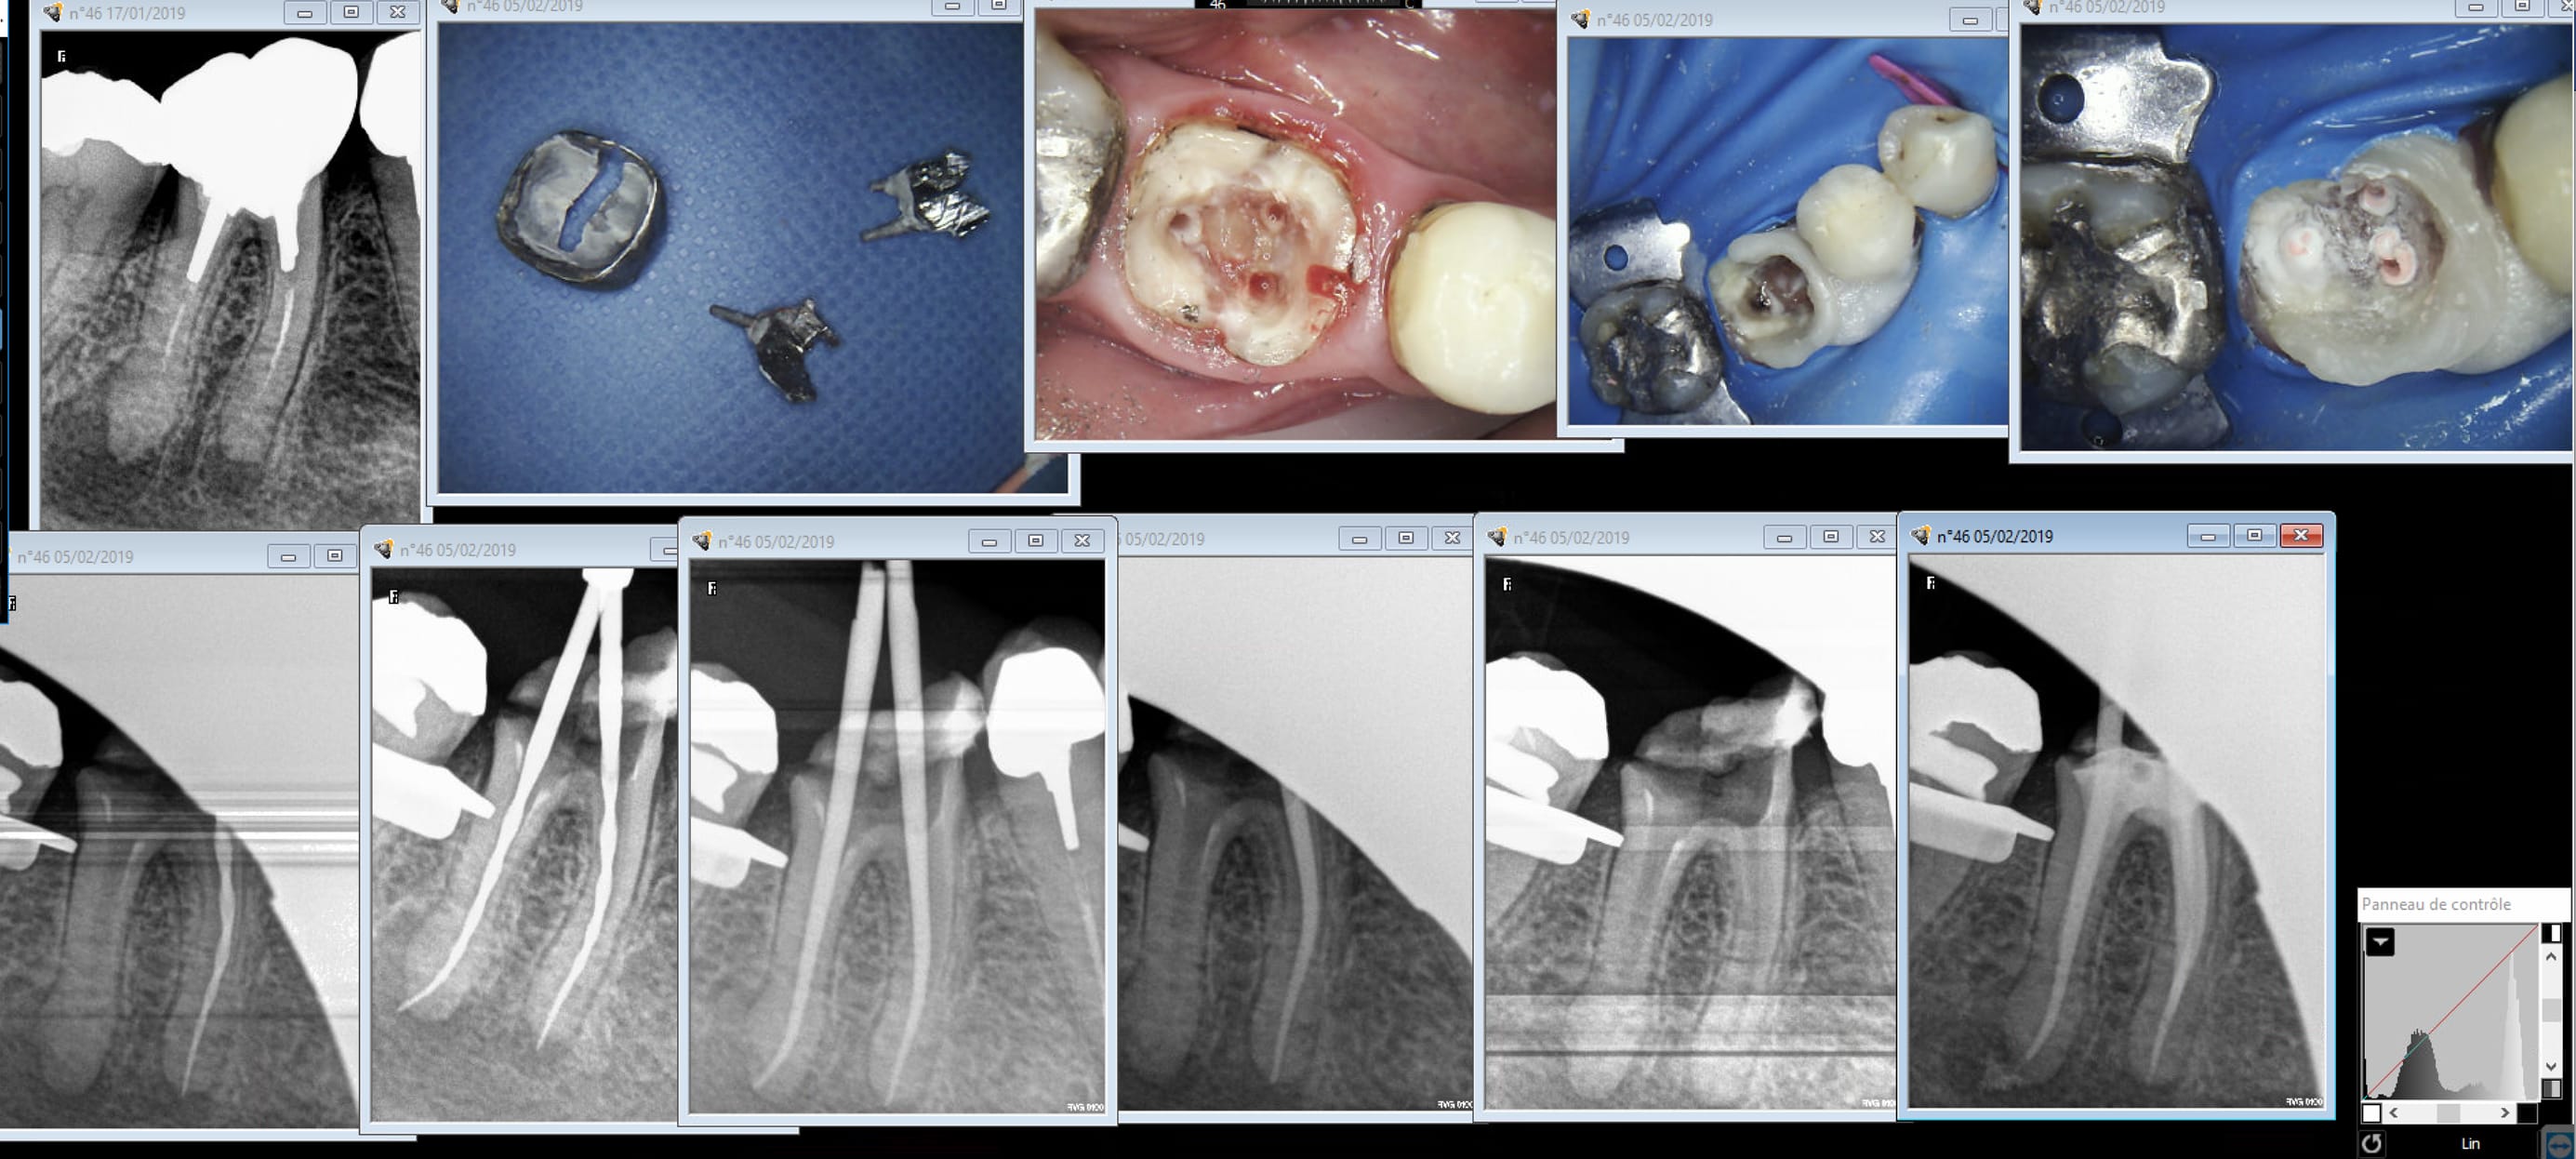

Figurez vous que j'ai eu le meme problème que notre confrère avec cette 27. Endo réalisée 7 ans auparavant. L'enfoiré de correspondant a dit qu'il y avait un problème alors que le patient ne sentait rien.

Capture d écran 2019 08 28 11.07 - Eugenol